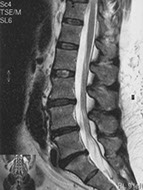

The images below depict degenerative lumbar disc disease:

Degenerative lumbar disc disease in the mature athlete. Degenerative changes of the lumbar spine, including decreased signal intensity and disc bulging at the L-3/4, L-4/5 and L-5/S-1 discs.